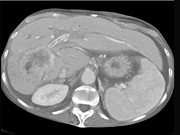

- 单项选择题男,50岁, 右上腹痛,进行性黄疸, 无腹部包块,AFP阴性, 影像检查如图,最可能的诊断为 ( )

D、胆管癌